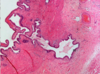

What feature is KEY to knowning that someone has had chronic cholecystitis?

mucosa dives into wall of the gallbladder, big sign of chronic cholecystitis. These are called Rokitansky-Aschoff sinuses (shown below)

Other Features:

You can have acute on chronic with neutrophils and scattered lymphocytes

Cholesterol can build in subepithelium of the gallbladder